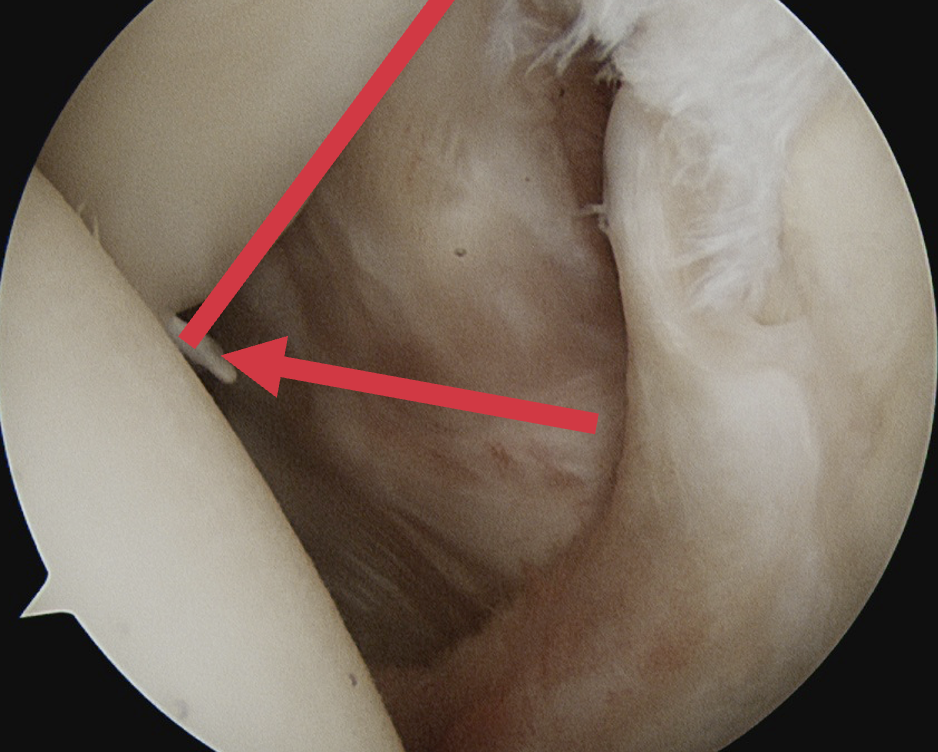

Comma sign

- medially retracted subscapularis tear

- exposes the superior insertion of superior glenohumeral ligament / coracohumeral ligament

Full thickness retracted subscapularis tear with comma sign